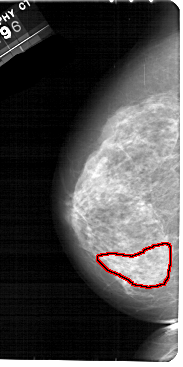

FILE: A_1885_1.LEFT_CC.OVERLAY

TOTAL_ABNORMALITIES 1

ABNORMALITY 1

LESION_TYPE CALCIFICATION TYPE PLEOMORPHIC DISTRIBUTION SEGMENTAL

ASSESSMENT 4

SUBTLETY 2

PATHOLOGY BENIGN

TOTAL_OUTLINES 1

BOUNDARY

A_1885_1.LEFT_CC

LEFT_CC LINES 5491 PIXELS_PER_LINE 2731 BITS_PER_PIXEL 12 RESOLUTION 43.5 OVERLAY